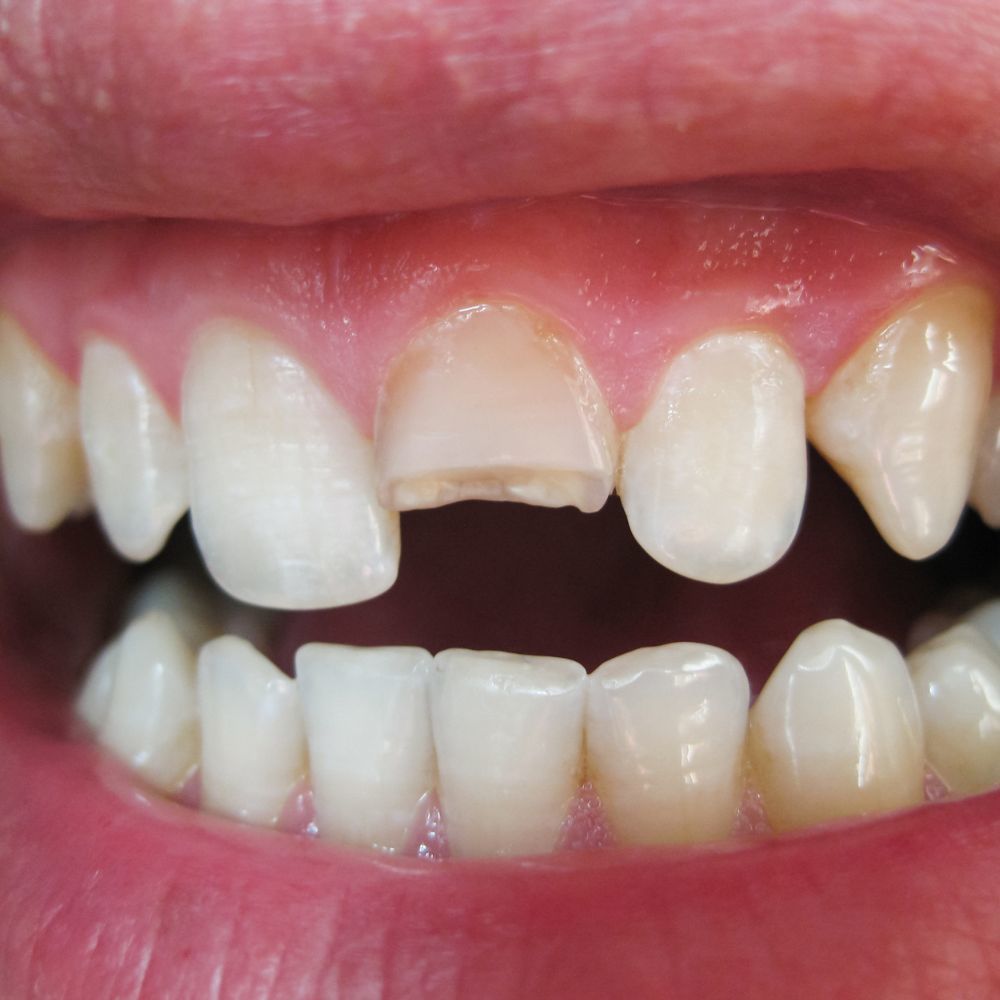

転んだ際に前歯が折れやすい

歯が出ているため、転んだり、何かにぶつかったりした際に、突出している前歯を強打しやすく、欠けたり折れたりするリスクが高くなります。